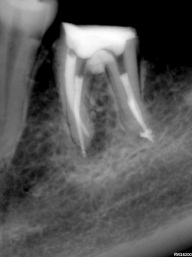

Perfurações dentarias são complicações no tratamento de canal que na maioria dos casos resulta em um prognóstico desfavorável, pois permite a entrada de microrganismos nos tecidos que envolvem o dente. Em alguns casos, devido ao seu difícil diagnóstico, acesso limitado, tempo decorrido ou tamanho da perfuração resultará em um desafio para o profissional conseguir um selamento adequado da área, sendo muito importante o conhecimento sobre o material que será empregado.